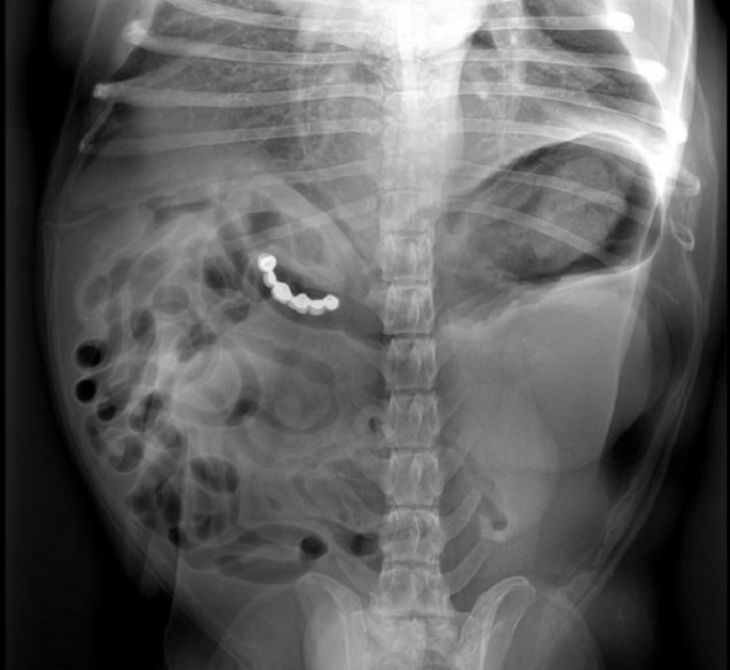

43 ponožiek

Pes prišiel na veterinárnu stanicu s veľkými bolesťami brucha, okamžite bol vykonaná snímka žalúdka, pretože vykazoval abnormálnu hmotnosť. Veterinár z neho následne chirurgickým zákrokom vybral 43 a pol ponožiek. Pes sa zotavil a zároveň veľmi rýchlo schudol.

(Zdroj: DoveLewis Animal Hospital via KPTV)